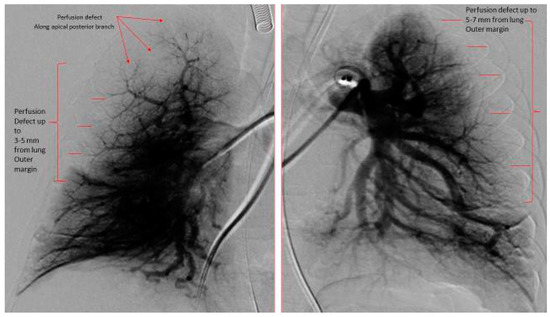

- Das, B.B.; Jadotte, M.M.; Mills, J.; Chan, K.C. Digital subtraction pulmonary angiography in children with pulmonary hypertension due to bronchopulmonary dysplasia. Med. Sci. 2019, 7, 26. [Google Scholar] [CrossRef] [PubMed]

| Pulmonary Vascular Underperfusion Score (PVUS) a (mean ± SD) | 2.66 ± 0.47 | 5 ± 0.81 | 0.0048 |